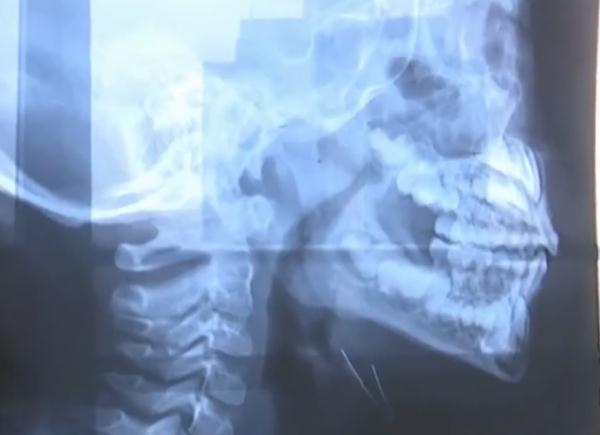

經(jīng)過(guò)醫(yī)生檢查

這名男孩是腺樣體肥大導(dǎo)致鼻子不通氣

習(xí)慣以口呼吸方式

代替鼻呼吸

自己的孫女剛做完腺樣體肥大手術(shù)

檢查后是因?yàn)橄贅芋w肥大

一般來(lái)說(shuō)腺樣體肥大超過(guò)三分之二

會(huì)影響孩子鼻呼吸

建議手術(shù)調(diào)節(jié)